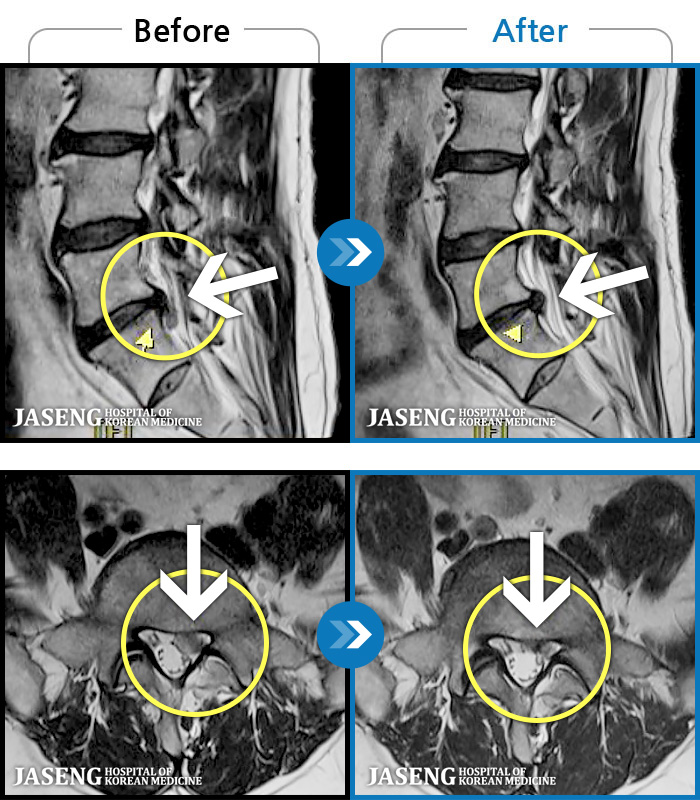

Before

After

양측 허리 묵직하고 뻐근한 통증, 우측 다리까지 이어지는 저림 증상 및 통증으로 내원하셨습니다.

2025.01.21 ~ 2025.11.18